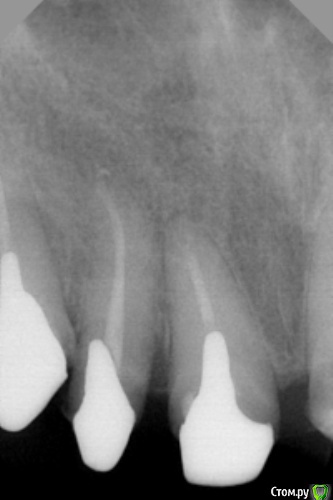

dr.Dre Опубликовано 13 июня, 2016 Поделиться Опубликовано 13 июня, 2016 Добрый вечер коллеги,делал тотальную работу под дугу металокерамики,вот одна из вкладок пошла в бок какой дальнейший прогноз? Ссылка на комментарий

chervoncevdaniil Опубликовано 13 июня, 2016 Поделиться Опубликовано 13 июня, 2016 (изменено) Я бы на вашем месте побеспокоился о очень короткой длине внутрикорневой части обеих вкладок,там реально риск расцементировок большой Изменено 13 июня, 2016 пользователем chervoncevdaniil Ссылка на комментарий

Art 7 Опубликовано 13 июня, 2016 Поделиться Опубликовано 13 июня, 2016 Судя по всему тканей над десной более чем достаточно, так что думаю будет все ок Ссылка на комментарий

chervoncevdaniil Опубликовано 13 июня, 2016 Поделиться Опубликовано 13 июня, 2016 Судя по всему тканей над десной более чем достаточно, так что думаю будет все окНу да,феррул в данной ситуации может проблему решить Ссылка на комментарий

joker_61rus Опубликовано 26 июня, 2016 Поделиться Опубликовано 26 июня, 2016 Как писали выше с гутаперчей проблем нет, канал нашел и ларго прошел. Я цемент приловчился ультразвуком проходить + твердосплавный шарик на микромотор+ развертки, когда время есть(работаю в госке) люблю поковыряться чтоб поглубже разобрать канал. То что на вашем снимке немного ушли-ничего страшного, перфо вроде нет, а вот длинна маловата конечно. Если работа только не стадии вкладок, я б переделал. Ссылка на комментарий